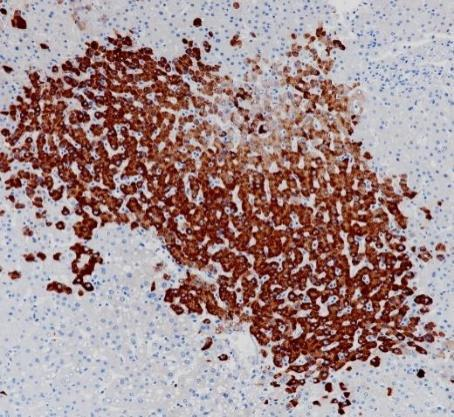

APOE Recombinant antibody

3315Uniprot ID:P02649 Organism: Rabbit Applications:IHC:1:200-1:800 IHC-Polymer:1:800-1:3200 IHC-TSA:1:1000-1:4000 IF:1:50-1:100...